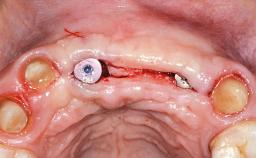

Replacement of Failing Hydroxyapatite-Coated Cylinder-Type Implants with Bone-Level Implants and a Screw-Retained Fixed Partial Denture in the Anterior Maxilla

This 49-year-old woman was referred for treatment by her general dentist with the request that she be evaluated for her “failing implants.” This very cooperative patient presented for care with no significant medical conditions, no known drug allergies, and was not taking any prescription medications. She did report a history of mild insomnia in the previous 7 years and was taking a multi-vitamin supplement in addition to over-the-counter vitamin D and calcium supplements. She complained of mild discomfort and swelling around her dental implants and occasional foul taste and unpleasant aroma in her mouth. A thorough history and examination revealed no evidence of parafunctional habits or temporomandibular joint disorder.